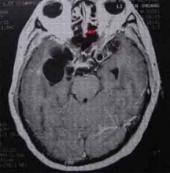

腦寄生蟲病治療

• 腦寄生蟲病

628健康網為您分享有關腦寄生蟲病的癥狀,腦寄生蟲病的治療方法,腦寄生蟲病的預防知識,腦寄生蟲病的癥狀圖片,腦寄生蟲病...